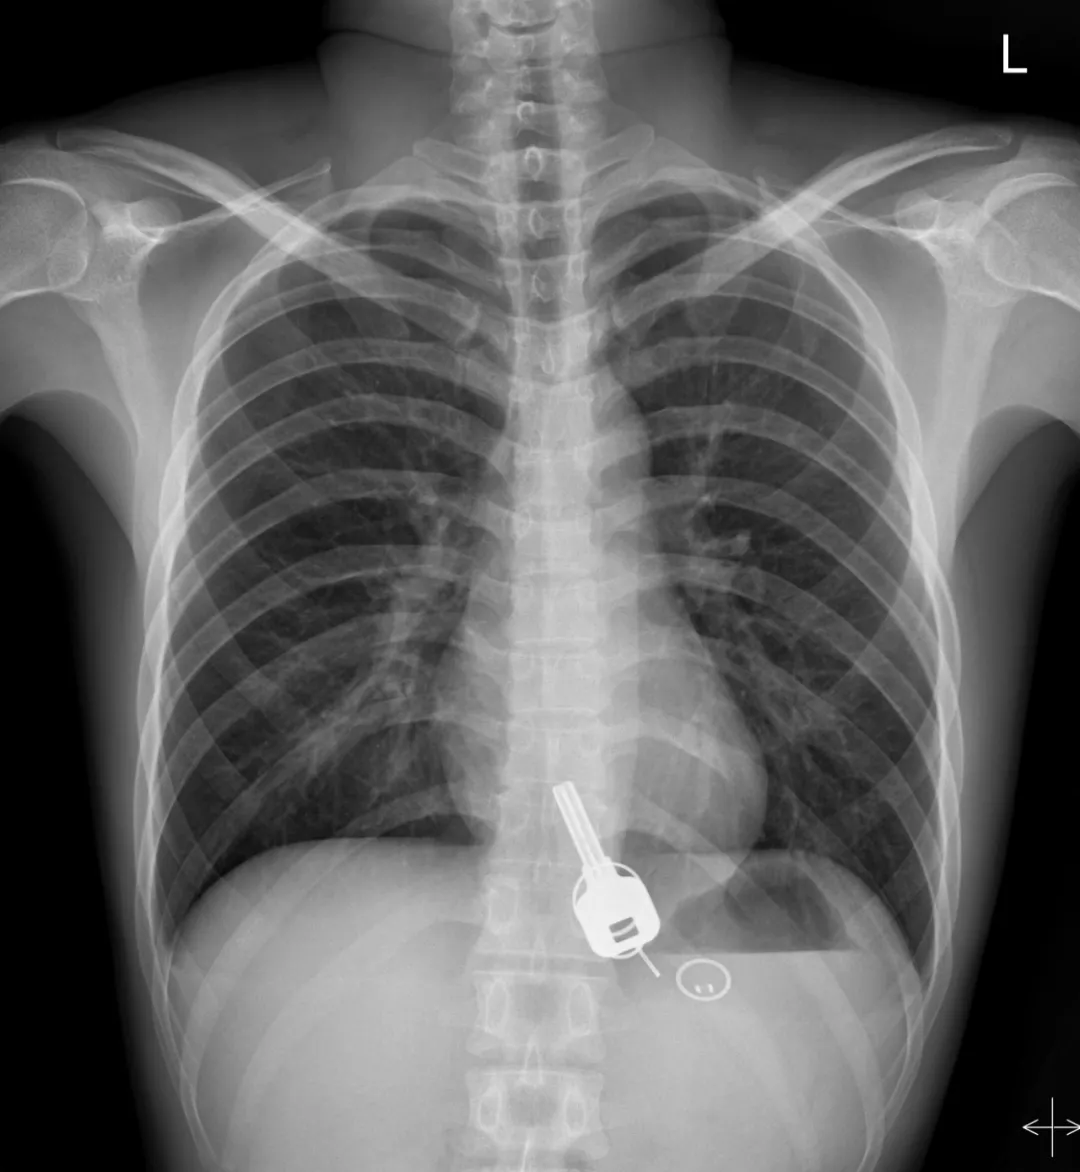

廣東東莞的常先生酒后回家找不到鑰匙,酒醒后他感到胸口疼痛,去醫(yī)院一查,發(fā)現(xiàn)一把鐵鑰匙、2個鑰匙扣、1個門禁牌清楚顯示在肚子胃區(qū)的位置上。

醫(yī)生準(zhǔn)備在胃鏡下取出鑰匙,不料,因鑰匙太大在常先生喉嚨附近食管入口處卡住了,取不出來,最后,醫(yī)生決定給常先生做無痛胃鏡,麻醉后,常先生食管入口處肌肉松弛,鑰匙終于順利取出!。